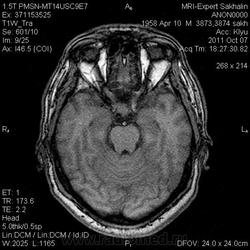

Аденома гипофиза

Вот такая аденома гипофиза сегодня.Мужчина с жалобами на снижение зрения.

постконтраст